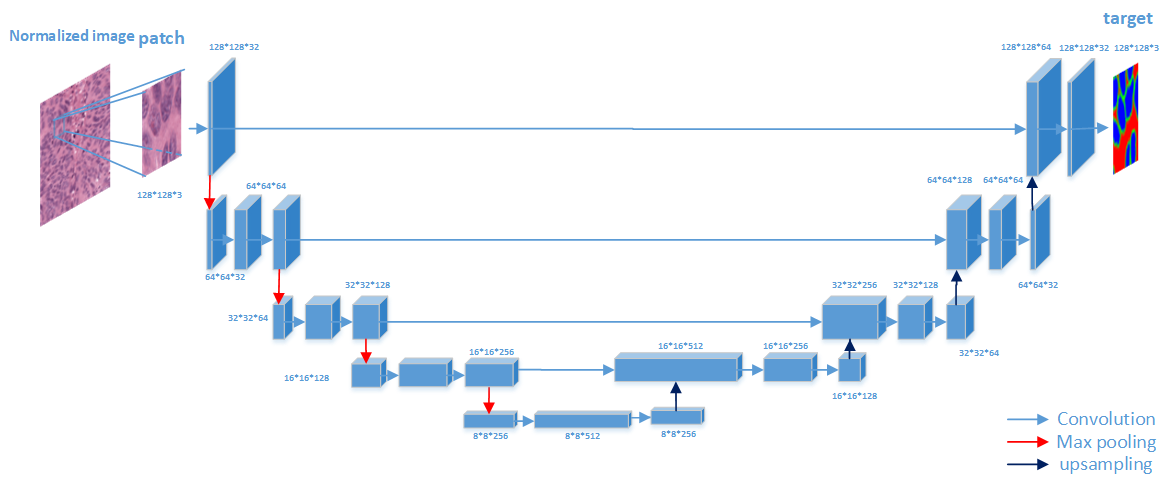

The task of nuclei segmentation can be roughly divided into two stages: the first stage is extracting the foreground(nuclei), the second stage is segmenting the connected foreground area into separated nuclei and finding out the boundary of each nucleus. Our method intends to merge these two steps by extracting the nuclei and their edges at the same time. That is the reason why it is named ”nuclei-boundary(NB) model”. As shown in Fig.3, the output of the NB model has three channels, each has the same height and width with the input image. Its values represent the probabilities of each pixel being , or class, respectively. The manual annotation for our segmentation problem is the boundary of each nucleus. A pixel belonging to the class means that it is on or inside an annotated boundary and within 2 pixel from the boundary. Pixels of the class are those that are inside annotated boundary but are not pixels. Correspondingly, the output can be regarded as an RGB image and the estimated maps of the , and are represented by red, green and blue, respectively, as shown in Fig.3. To generate the ternary mask for training, we apply a morphology operator to each nucleus to obtain the pixels, and then subtract pixels from the nucleus to get pixels.

II-C1 The architecture of our NB network

Fig.3 shows the network architecture of our algorithm, which consists of a couple of encoding and decoding layers. The encoding layers are used to extract different levels of contextual feature maps. The decoding layers are designed to combine these feature maps produced by the encoding layers to generate the desired segmentation maps. Due to the memory limitation of our GPU, the size of the input layer is set to 128X128 in our experiments. But we noticed that larger input layer may lead to better performance. The weight of each convolutional layer is initialized by glorot uniform[28] and bias is initialized to 0. The glorot uniform is defined as: